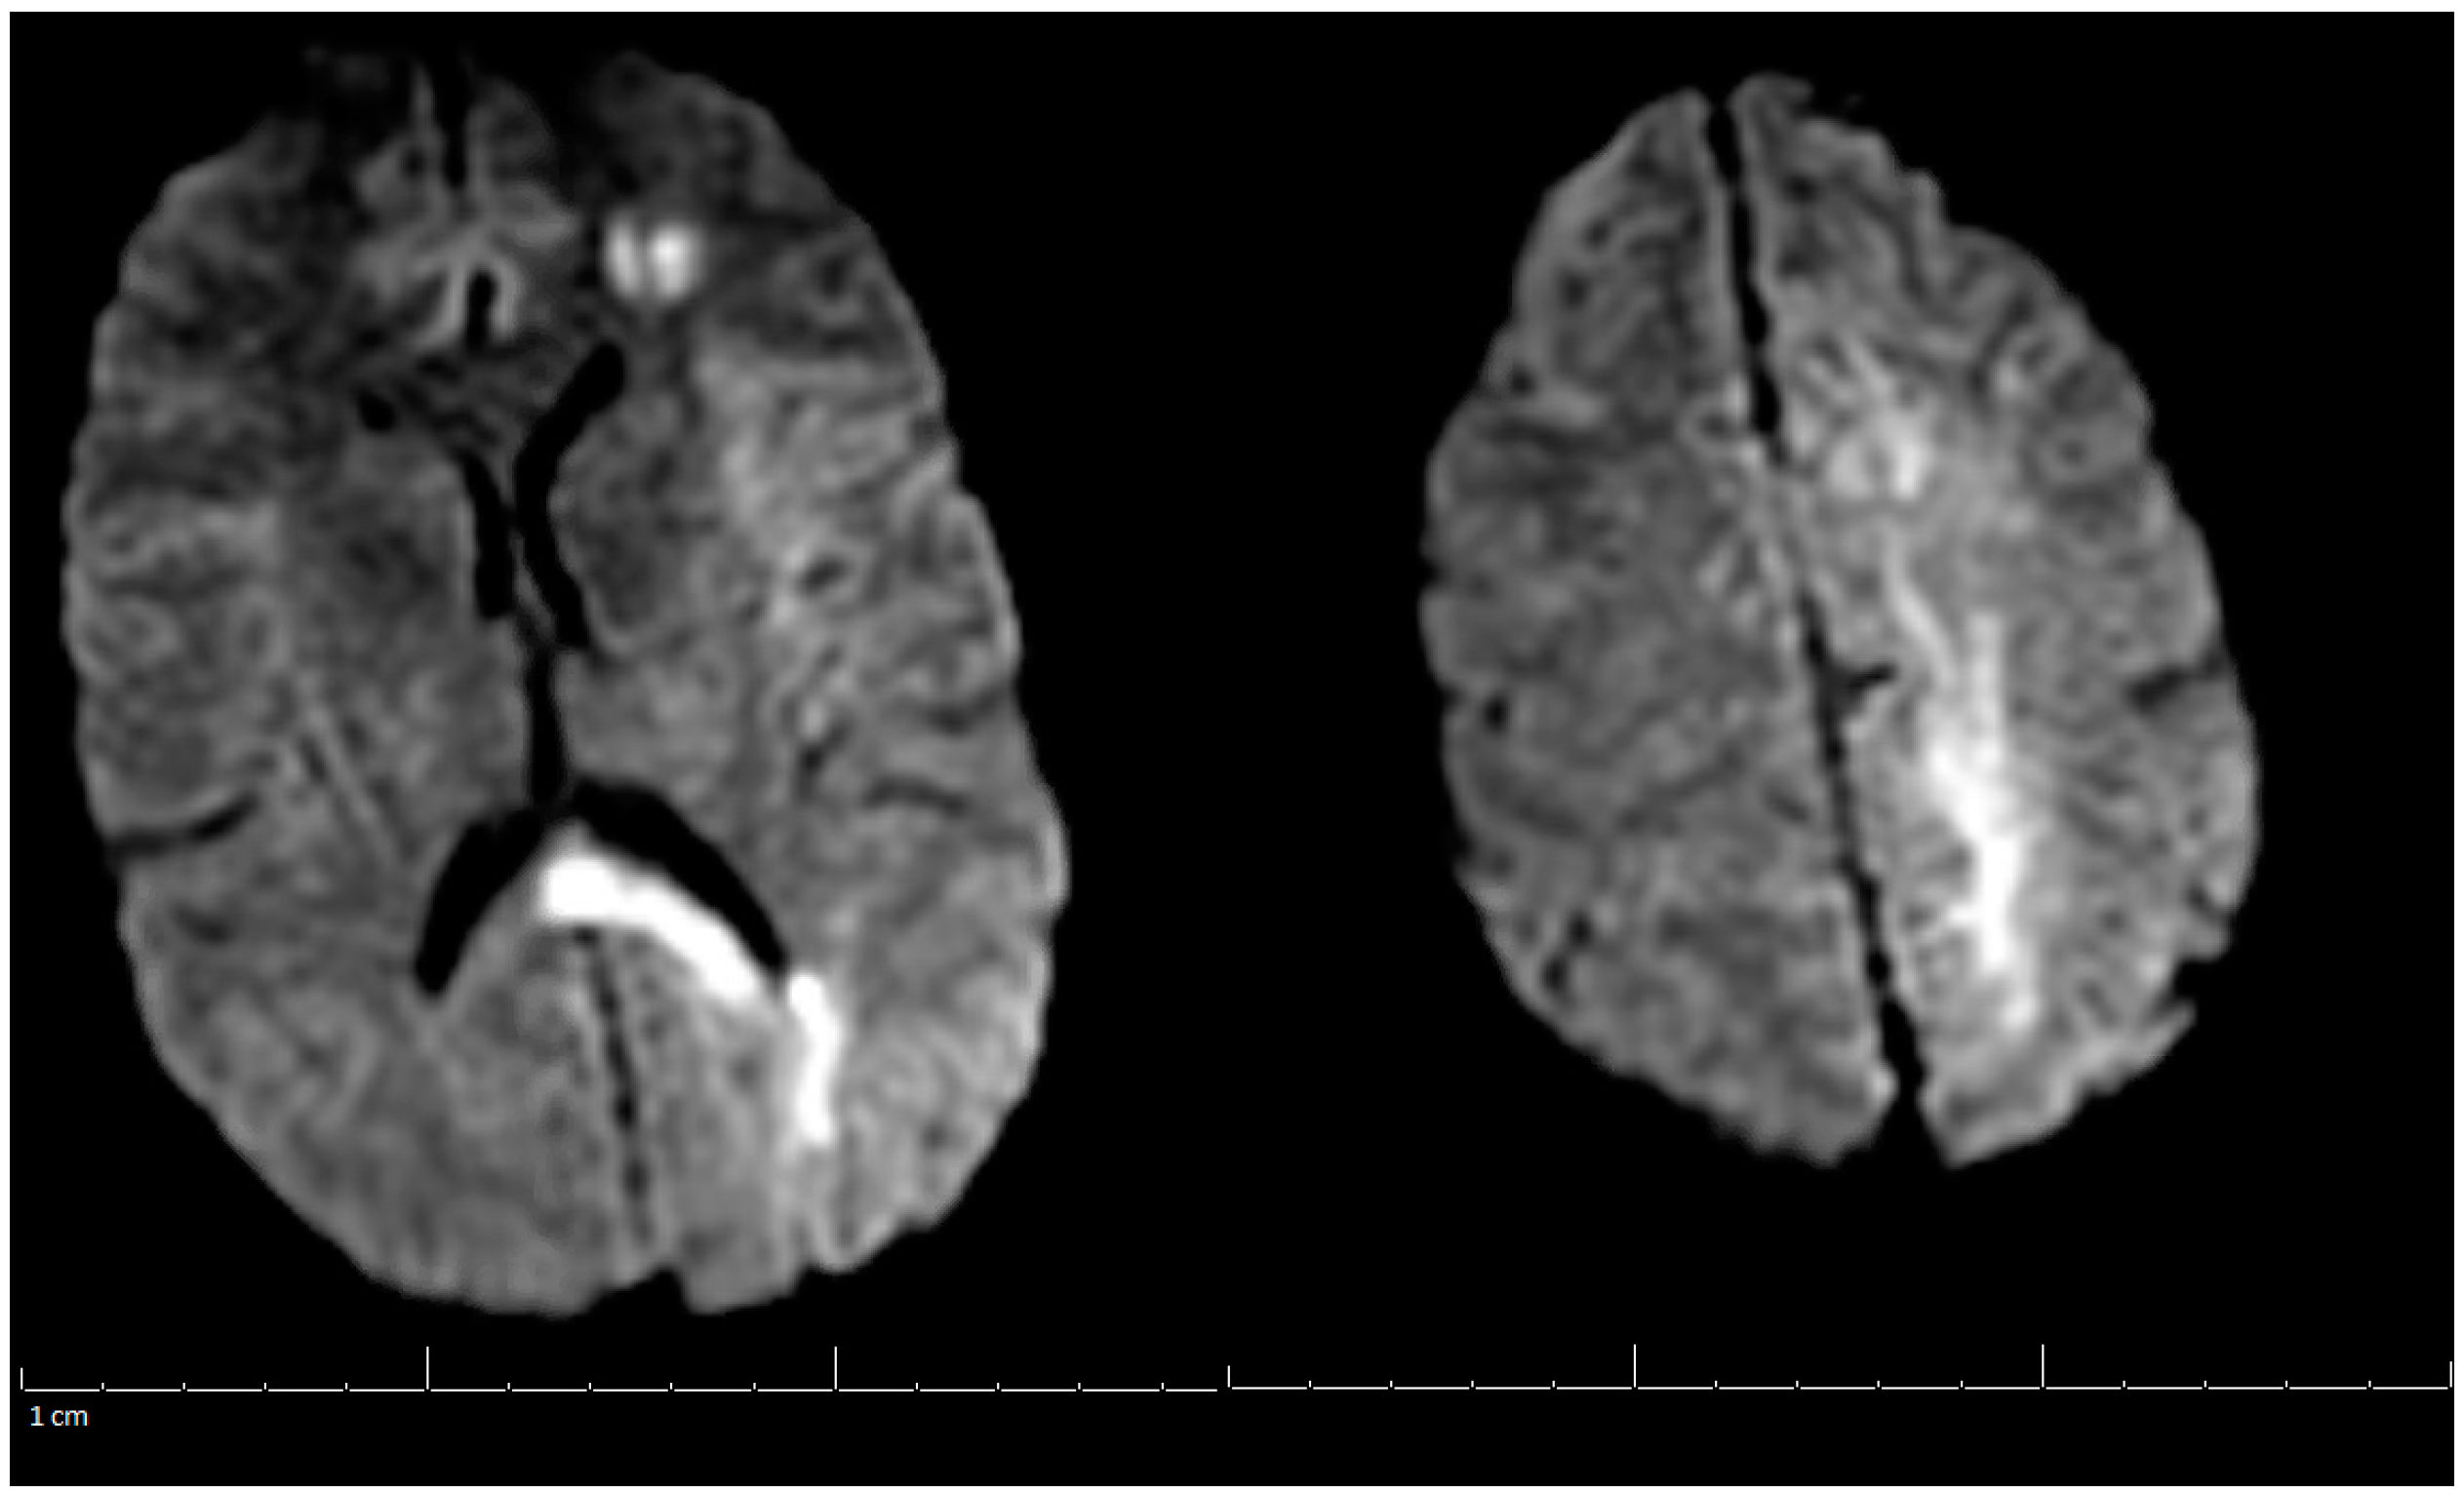

Additional labs showed Complete Blood Count (CBC) within acceptable limits, Basic Metabolic Panel (BMP) significant with glucose of 142 mg/dL, normal cardiac troponin level, and a negative urine drug screen. Urinalysis showed a small amount of blood but no evidence of infection. Genetic hypercoagulable labs, including antinuclear antibody, antineutrophil cytoplasmic antibodies, anti-cardiolipin, anti-Beta-2-glycoprotein, Factor V Leiden, and a lupus anticoagulant assay, were also unremarkable. Several hypercoagulable tests including antithrombin, protein C, and protein S were deferred, as results would have been confounded by the acute thrombotic event. Of note, the patient had abnormal findings on the lipid panel consisting of high cholesterol, triglyceride, and VLDL, and a low HDL level. Ultrasound Venous Doppler of the bilateral lower extremities showed no deep vein thrombosis. MRI brain/MRV (Magnetic Resonance Imaging (MRI) is a technique that uses magnetic fields and computer-generated radio waves to create images of organs and tissues in your body. Magnetic Resonance Venography (MRV) uses magnetic resonance technology and intravenous contrast dye to visualize the veins. Diffusion-Weighted Imaging (DWI) is a form of MRI that uses the diffusion of water molecules to generate images) with and without contrast confirmed acute venous infarct in the left subcortical frontal and parietal lobes as well as the left splenium of the corpus callosum. Thrombosis of the superior sagittal sinus, cortical veins, straight sinus, left internal cerebral vein, vein of Galen and the bilateral transverse sinuses, as well as the left sigmoid sinus, were also confirmed. A small hemorrhagic focus in the left occipital lobe was noted and was likely venous hemorrhages (Figure 1 and Figure 2). The final diagnosis was diffuse cerebral venous sinus thrombosis likely related to OCP use with possible contribution by recent COVID vaccination.

Figure 1.

MRI of the Brain without contrast (DWI) (Magnetic Resonance Imaging (MRI) is a technique that uses magnetic fields and computer generated radio waves to create images of organs and tissues in your body. Magnetic Resonance Venography (MRV) uses magnetic resonance technology and intravenous contrast dye to visualize the veins. Diffusion-Weighted Imaging (DWI) is a form of MRI that uses the diffusion of water molecules to generate images).